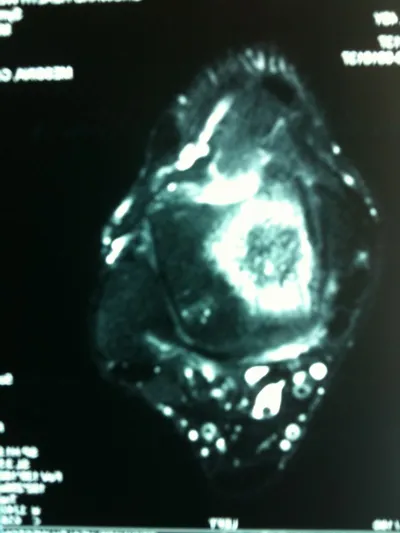

Series of Pics of Microfracture of large OCD of the Talar Dome

Pic of OCD after preparation and debridement .

Measuring the size and depth of the OCD.